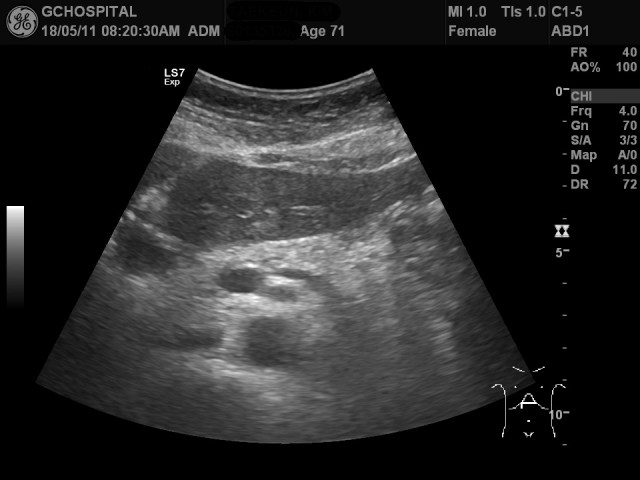

올해에도 췌장낭종의 추적관찰을 위해 내원하셔서 췌장부위를 촬영한 게 위의 영상입니다. 그런데, 영상에서 췌장낭종이 확인되지 않고 있습니다.

뿐만 아니라 췌장의 꼬리부위에 흐릿하게 저에코음영이 있는것처럼 보이기도 합니다. 과연, 췌장에 저에코의 종괴나 췌장염과 같은 병변을 의심해야 하는걸까요?